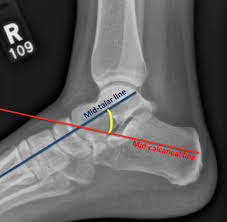

Talocalcaneal angle(30-55도, dorsiflexion lat시 25~50도) 이나 Talo-1st MT angle(5-15도), tibiocalcaneal stress lateral angle(10~40도) 를 시행해 볼 수 있습니다.

Talocalcaneal angle은 Lat 에서 감소하거나 음각이 되기도 합니다.

Tibiocalcaneal stress lateral angle 은 만곡족에서는 음각입니다.

Talocalcaneal index : 전후면 거종각 + 측면 거종각을 합한 수치로 (40도 이상 정상), 만곡족시 40도 이하가 됩니다.